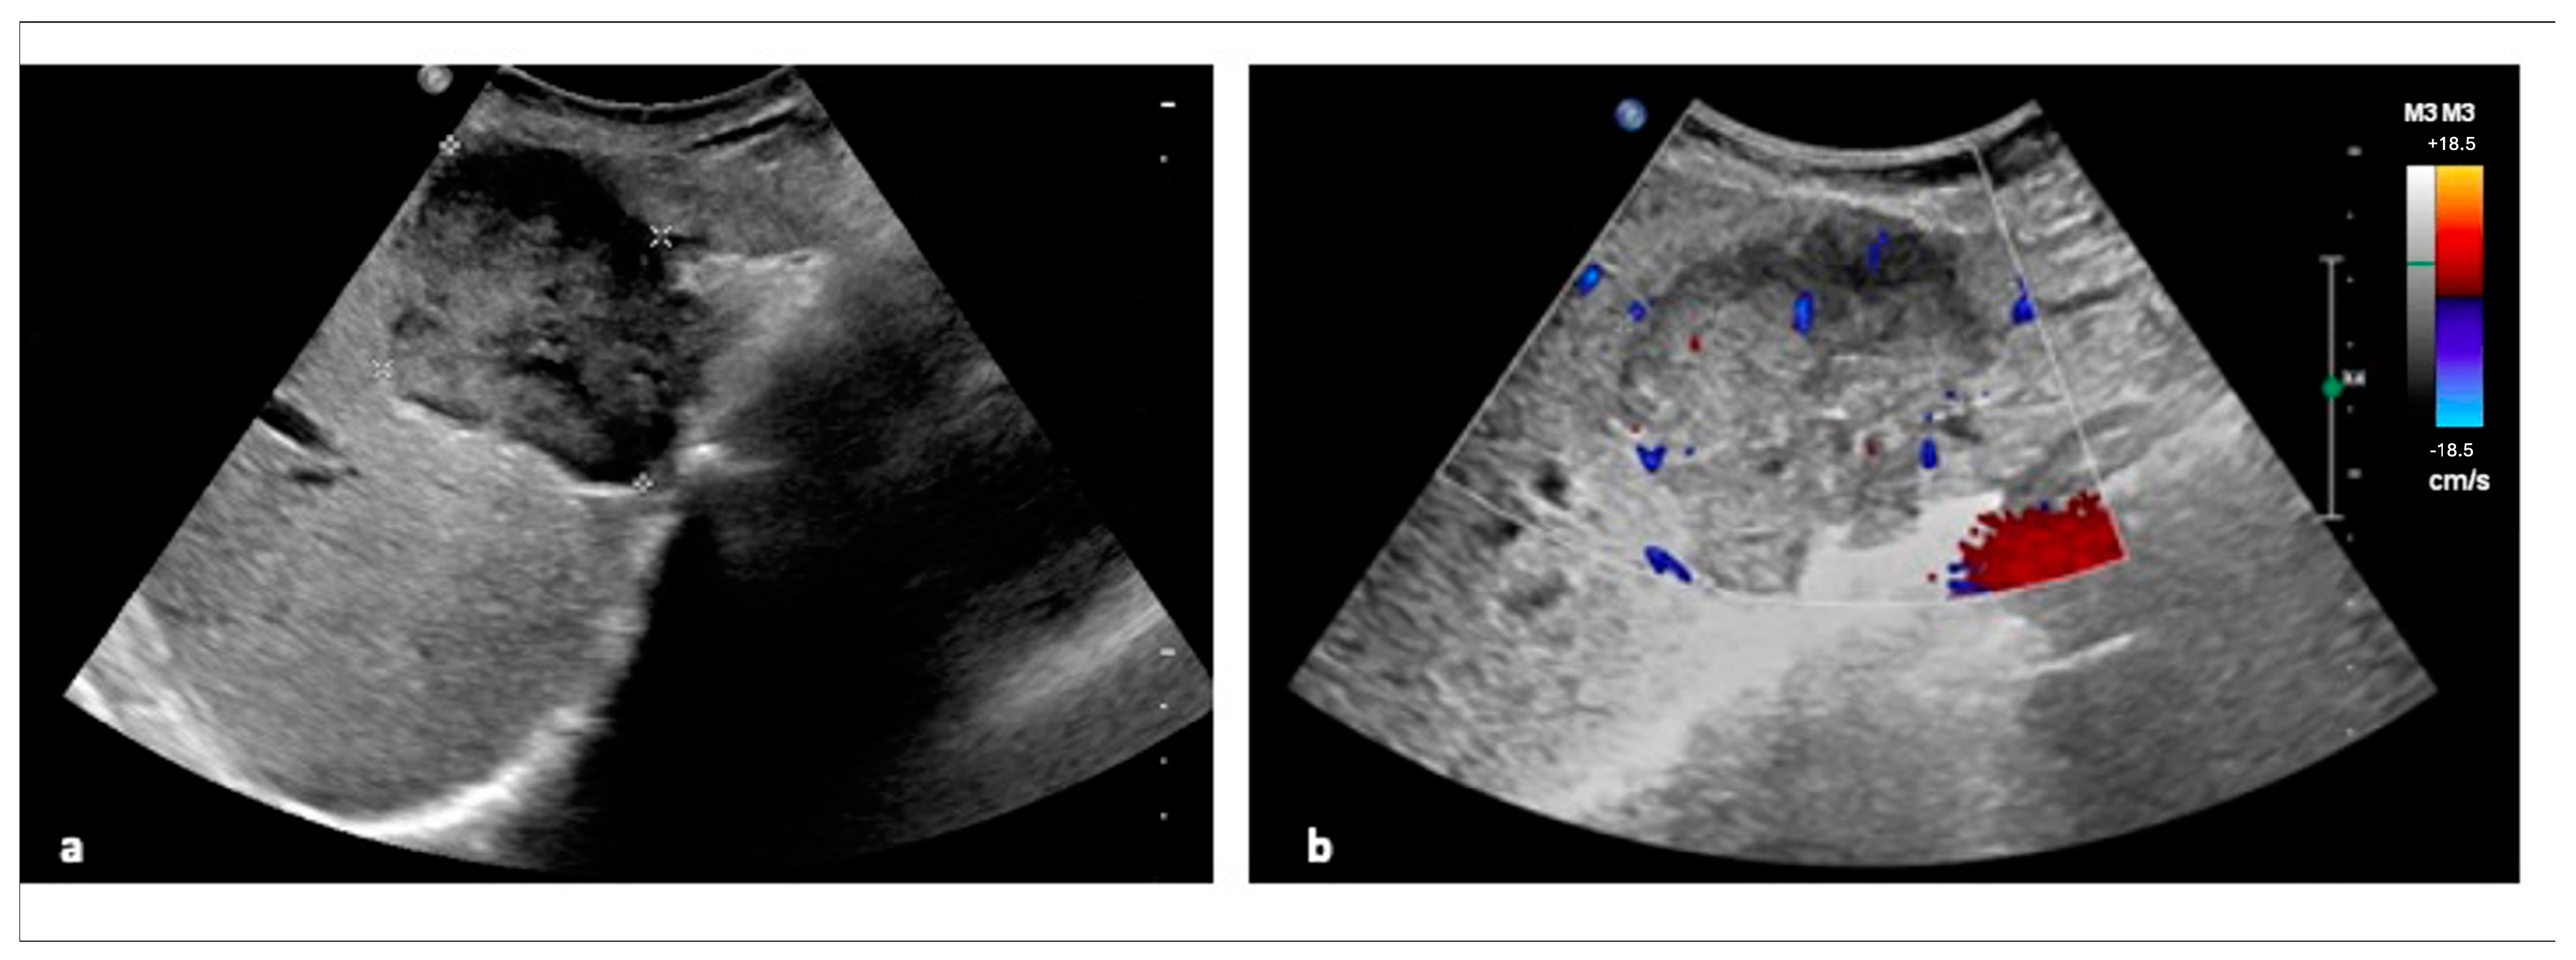

2.1. Ultrasonography (US)

- Guo, L.H.; Xu, H.X. Contrast-Enhanced Ultrasound in the Diagnosis of Hepatocellular Carcinoma and Intrahepatic Cholangiocarcinoma: Controversy over the ASSLD Guideline. Biomed. Res. Int. 2015, 2015, 349172. [Google Scholar] [CrossRef]